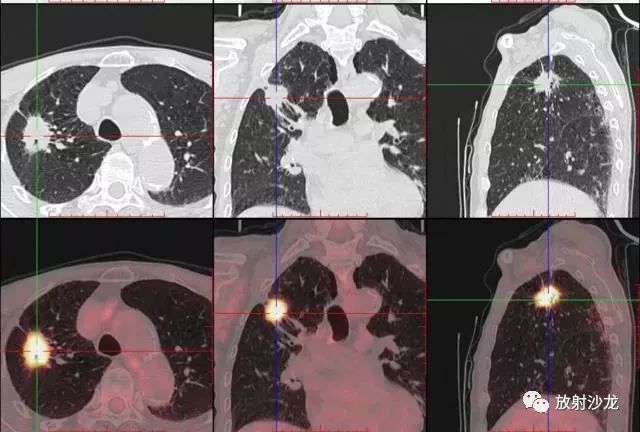

PET-CT等于PET+CT,包含PET(功能分子影像)與CT(解剖影像)的最優(yōu)化組合;即同時(shí)具有PET和CT的功能,但它絕不是二者功能的簡(jiǎn)單疊加,因為PET與CT優(yōu)勢互補,“1+1>2”。PET-CT除了具備PET和CT各自的功能外,其獨有的融合圖像,將PET圖像與CT圖像融合, 可以同時(shí)反映病灶的代謝,可以早期診斷疾病的同時(shí),明顯提高診斷的準確性。